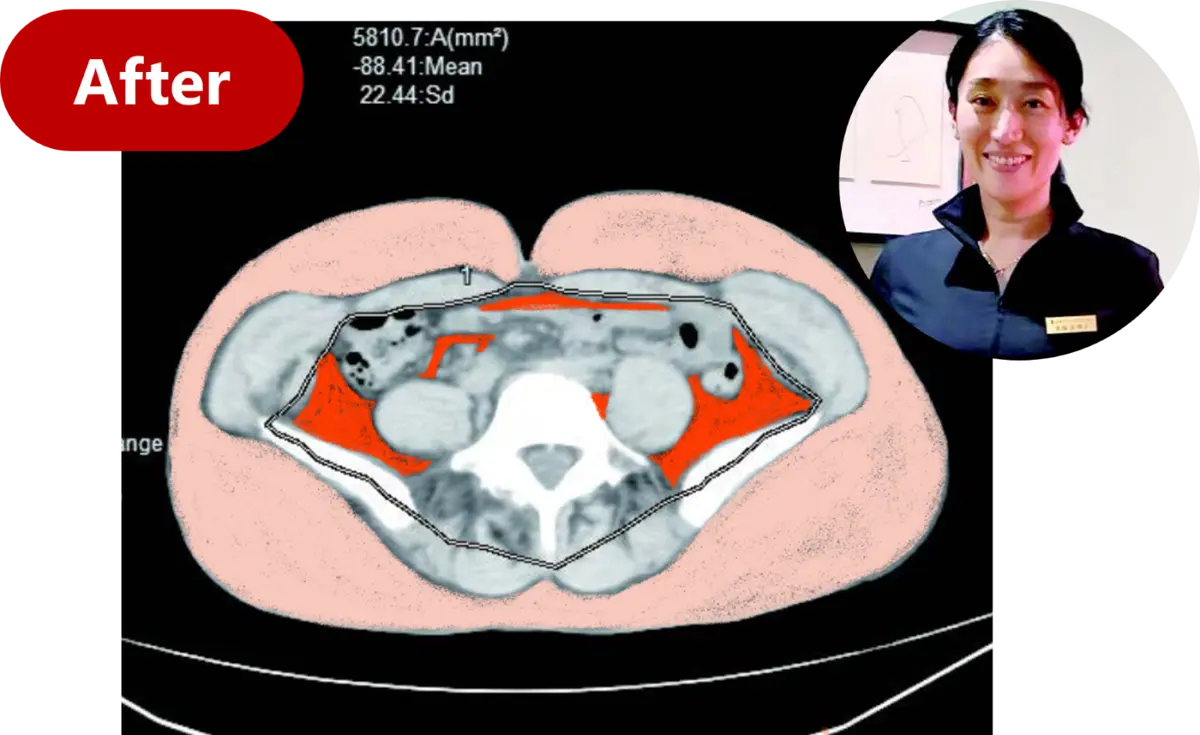

以下が、齋藤先生が〈齋藤式満腹やせメソッド〉を行う前と、行って1カ月たった頃のCTスキャンの比較画像。

白いところが骨、灰色がかったところが筋肉。筋肉の外側を覆っている黒いかたまりが皮下脂肪で、その内側の黒い部分が内臓脂肪。内臓脂肪と皮下脂肪を含めた脂肪の面積が、1カ月で16.47㎠も減少。

OurAge×Webエクラ AFTER 内臓脂肪……  58.10㎠ 皮下脂肪……245.41㎠ 合計 …………303.51㎠

脂肪の面積が1カ月で−16.47㎠! 体重が2カ月で−6Kg!